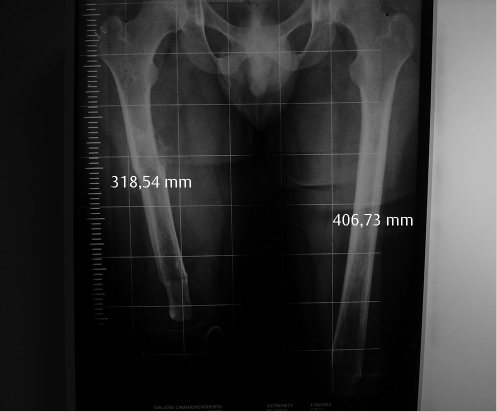

The recipient was a 22-year-old man, who was a wheelchair-dependent bilateral traumatic AK amputee. The right side level was mid-shaft femur, and left side was the distal third (▶ Fig. 25.1). CMV immunoglobulin G (IgG) was negative and Epstein–Barr virus (EBV) IgG was positive. The donor was a 26-year-old woman ABO-compatible multiorgan donor. CMV and EBV IgG were negative, and there was total HLA mismatch—and a complete human leukocyte antigen (HLA) mismatch. Transplantation was performed on July 11, 2011, by a single surgeon with three assistants. Relevant structures were dissected and tagged bilaterally in the stumps of the recipient. The external iliac vessels were used as the recipient vascular sites. The procurement of the legs was performed in an adjacent operating room after cardiac and liver retrieval. The infrarenal aorta was not cross-clamped, allowing simultaneous in situ perfusion of the lower extremities with cold UW (University of Wisconsin) solution.